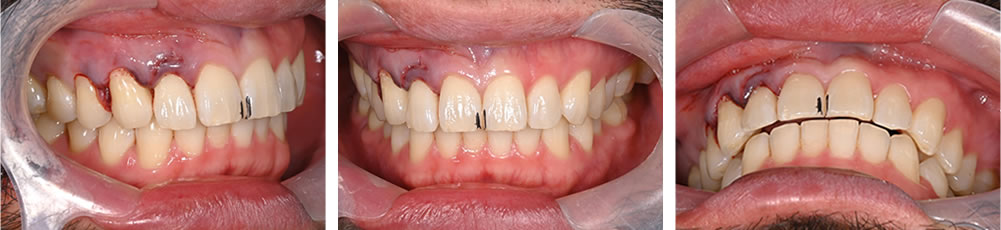

歯の復位

受傷前の写真を参考に、歯を正しい位置に戻しました。

歯の固定

歯を正しい位置に戻した後、ワイヤーにて固定を行いました。